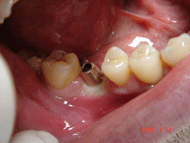

| <症例4> |

| 右下6番パーフォレーションによる骨吸収のため抜歯。両隣在歯がノンカリエスのためインプラントを選択。 |